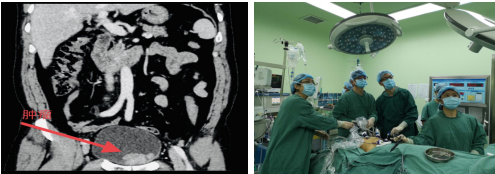

2020年12月6日,患者,男,70岁,因“膀胱癌复发血尿1月”来到州人民医院就诊后入住外二科,入院后经详细检查,经完善相关术前检查、术前准备后,由科主任喻定刚主任医师主持进行了全科讨论,为减少患者创伤,依托本科十多年腹腔镜手术经验,计划于12月10日为患者在全麻下行腹腔镜下膀胱癌根治术。12月10日,在手术室麻醉老师团队的协助下,由喻定科主任主刀、罗斯满主任医师、尕藏东周主治医师助手,经默契配合下按术前讨论计划成功完成“腹腔镜下膀胱根治切除术+标准淋巴结清扫+Studer膀胱术”。

(患者术前CT检查) (手术中)

该患者病情危重,病灶需要切除的范围广,该手术操作复杂涉及泌尿、生殖和消化系统,手术难度大,是泌尿外科难度最大的手术之一。

此次通过微创术式治疗膀胱癌,在阿坝州开展是首例,此类腹腔镜手术与开放性手术相比较,患者在术中出血量少、输血率低、胃肠功能恢复快、术后镇痛药用量少,住院时间短。通过手术对肿瘤切除彻底,患者复发率低,远期效果好,为患者减轻了痛苦。